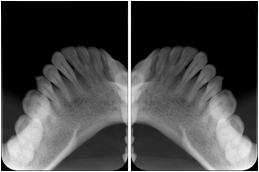

Intra-oral radiography typically involves acquisition of multiple images of various parts of the dentition. Many digital radiographic systems offer customized templates that are used for displaying the images in a study on the screen. These templates may also be referred to as mounts or view sets. The Structured Display Object represents a standard method of encoding and exchanging the layout and intended display of Structured Displays. A structured display object created in this manner could be stored with a study and exchanged with images to allow for complete reproduction of the original exam.

1. A patient visits a General Dentist where a Full Mouth Series Exam with 18 images is acquired. The dentist observes severe bone loss and refers the patient to a Periodontist. The 18 images from the Full Mouth Series along with a Structured Display are copied to a DICOM Interchange CD and sent with the patient to see the specialist. The Periodontist uses the CD to open the exam in his Dental Radiographic Software and consults via phone with the General Dentist. Both are able to observe the same exam showing the images on each user's display using the exact same layout.

Intra-oral Full Mouth Series Structured Display

Figure OO-1. Intra-oral Full Mouth Series Structured Display